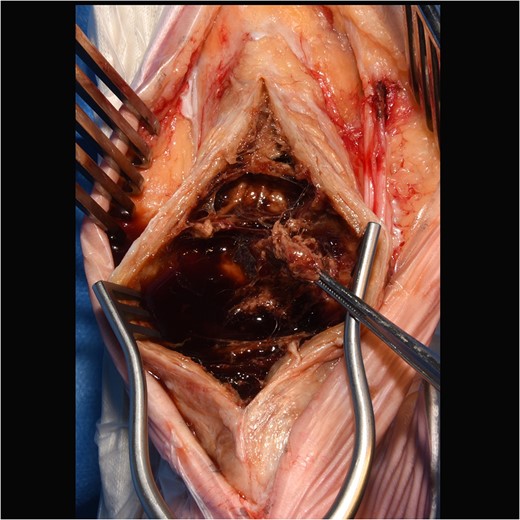

He underwent surgery to explore the tendon where an irregular, cystic, fibrofatty lesion was identified within the tendon (Figs 3–5). This was successfully resected and sent for histology which showed a florid granulomatous and histiocytic response to the suture material, in keeping with a suture granuloma (Figs 6 and 7). There was histological evidence of the abscess extending into the muscle (Fig. 8).

Intraoperative image of large cystic swelling over Achilles tendon.

Intraoperative image showing internal cystic granuloma within Achilles.